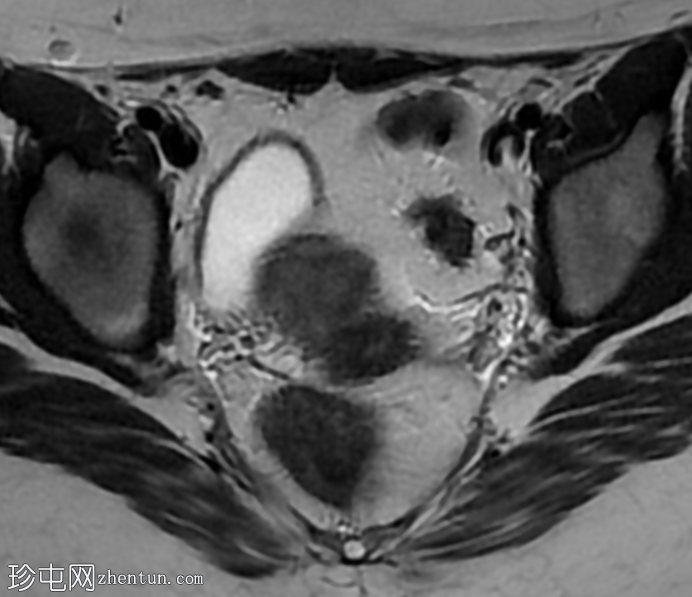

轴位

T2加权像

T1加权像

子宫体积较小,最大横径、前后径和头尾径均为3.0 x 3.0 x 2.7 cm。子宫体与宫颈的比例为1.3:1。子宫无明显分区结构。

双侧卵巢发育不良,无卵泡活动。